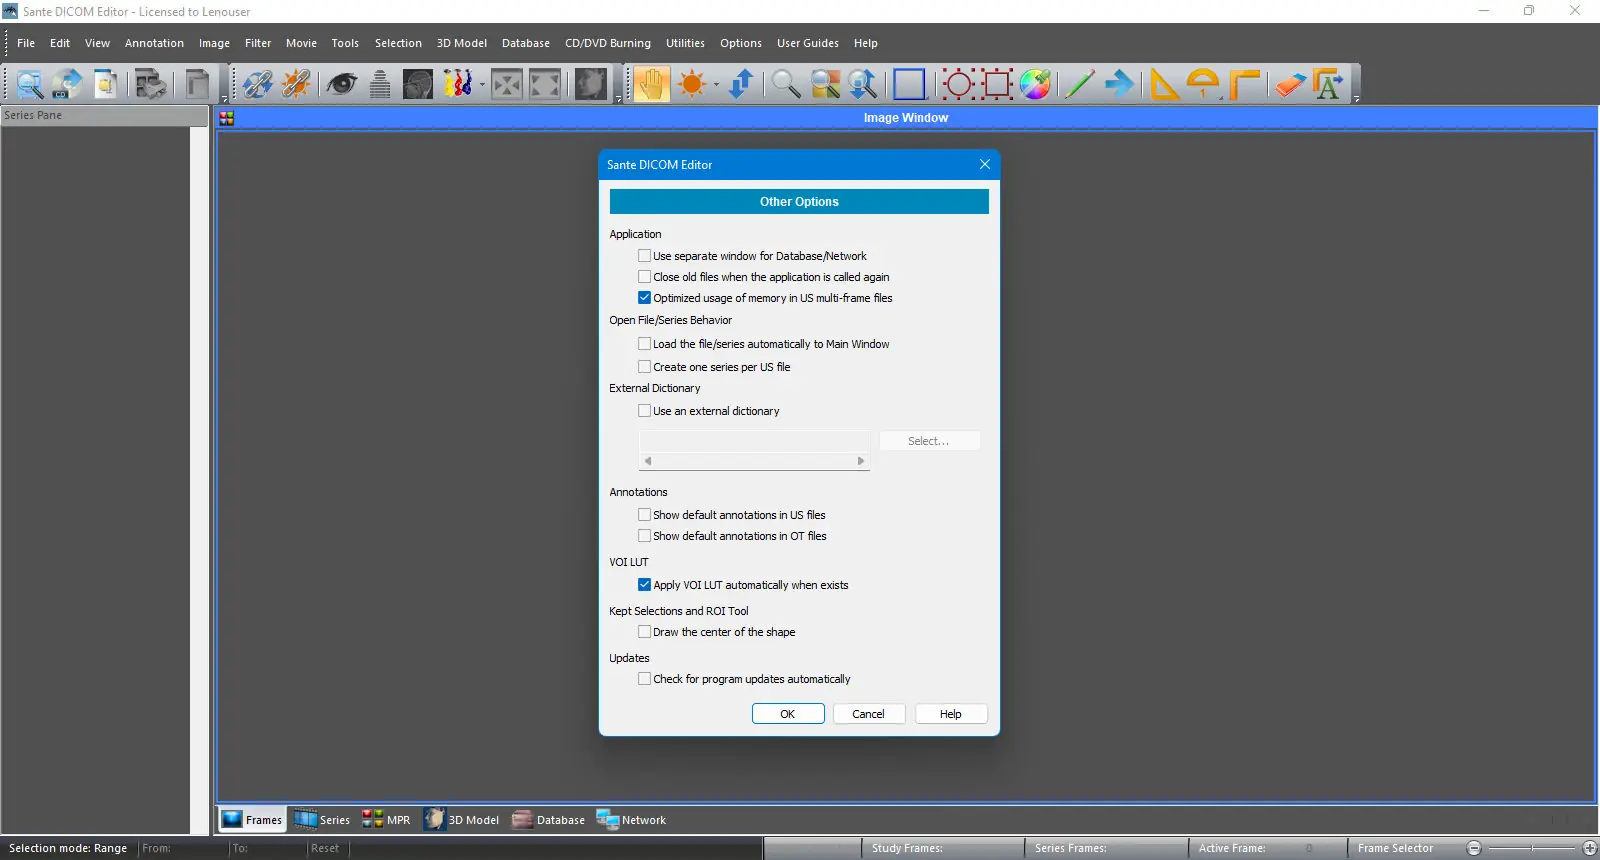

Интерфейс программы выполнен в классическом стиле Windows, что обеспечивает интуитивно понятное управление даже для пользователей без технического опыта. После установки можно импортировать DICOM-файлы напрямую с носителей, с сетевых устройств или через подключение к PACS-серверу. Редактирование атрибутов, включая вложенные последовательности, осуществляется через встроенный редактор заголовков с возможностью применения шаблонов для массовых изменений.

Программа представляет собой комплексное решение для обработки медицинских изображений, сочетающее в себе возможности мощной рабочей станции, поддерживающей2D и3D визуализацию. Она позволяет не только просматривать и редактировать файлы DICOM, но и выполнять сложные операции, такие как создание трёхмерных моделей методами isosurface, объёмного рендеринга и проекции максимальной интенсивности. Поддержка всех распространённых кодировок делает её пригодной для использования в международных медицинских учреждениях, включая те, где применяются кириллица, арабский или азиатские символы.